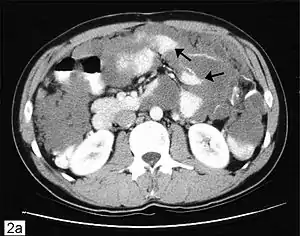

| Computed tomographic scan of an abdomen showing pseudomyxoma peritonei with multiple peritoneal masses (arrow) with "scalloping effect" seen. | |